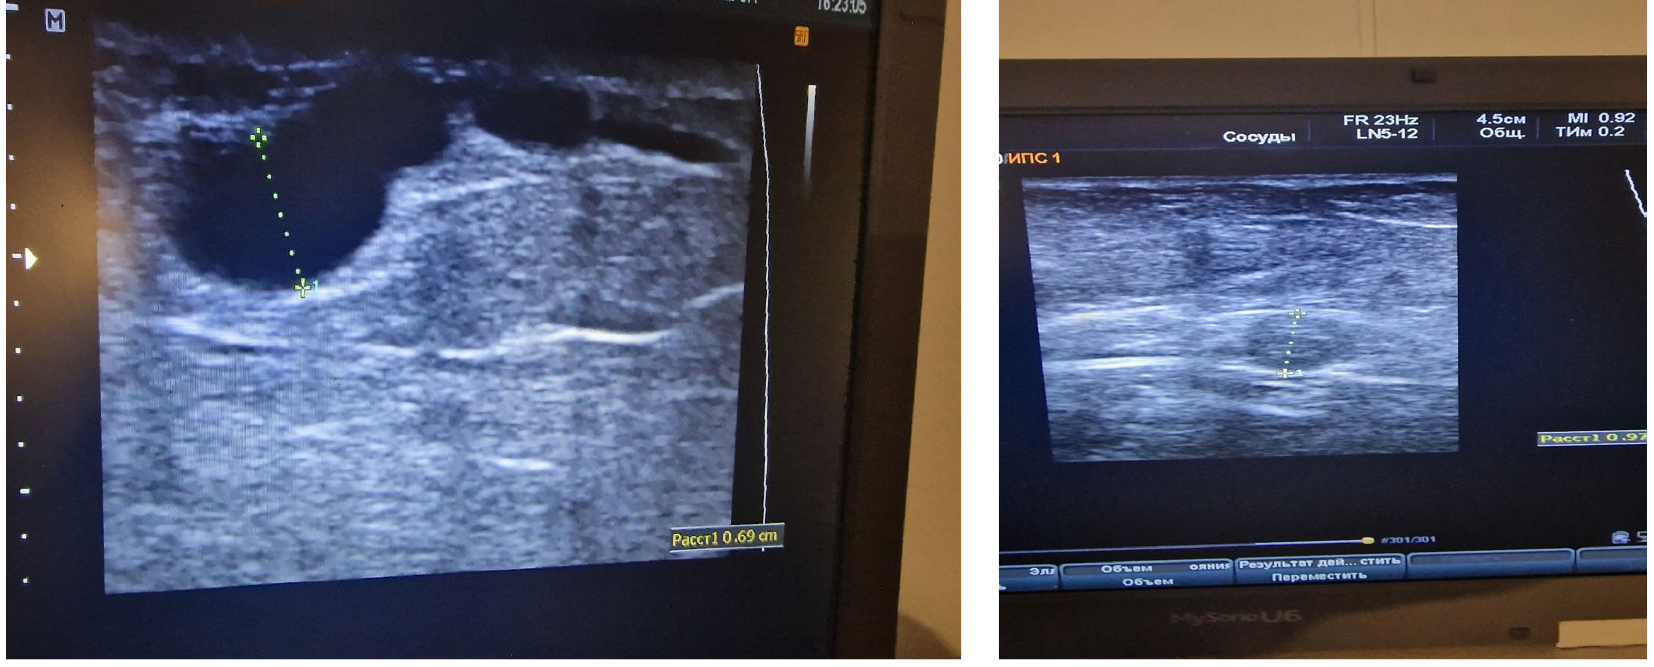

При осмотре нижних конечностей выявлены варикозные изменения поверхностных вен. Пациентке проведено ультразвуковое исследование вен нижних конечностей. В глубокой вене бедра выявлен флотирующий тромб (рис. 1 а), поверхностные вены расширены (рис. 1 б), кровоток в коммуникантах инверсирован.

Рис. 1. Данные УЗИ вен нижних конечностей. Флотирующий тромб в системе глубокой бедренной вены: а – варикозно расширенные поверхностные вены нижней конечности; б – источник ТЭЛА, глубокая венозная система ноги (пристеночная часть тромба, оставшаяся после случившейся эмболии)